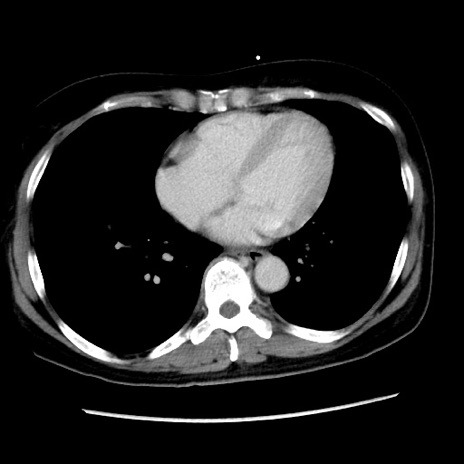

症例10(横断像)

【症例】 50歳代女性

【主訴】 腹痛

【現病歴】前日生レバーを食べた。今朝に排便あり。 昼前に突然発症の腹痛を生じ、当院救急外来を受診した。

【既往歴】 子宮筋腫にてで子宮全摘後

【身体所見】 意識清明、腹部:平坦、軟、下腹部やや左を中心に圧痛・反跳痛あり、筋性防御あり

【データ】WBC 7800、CRP 0.07